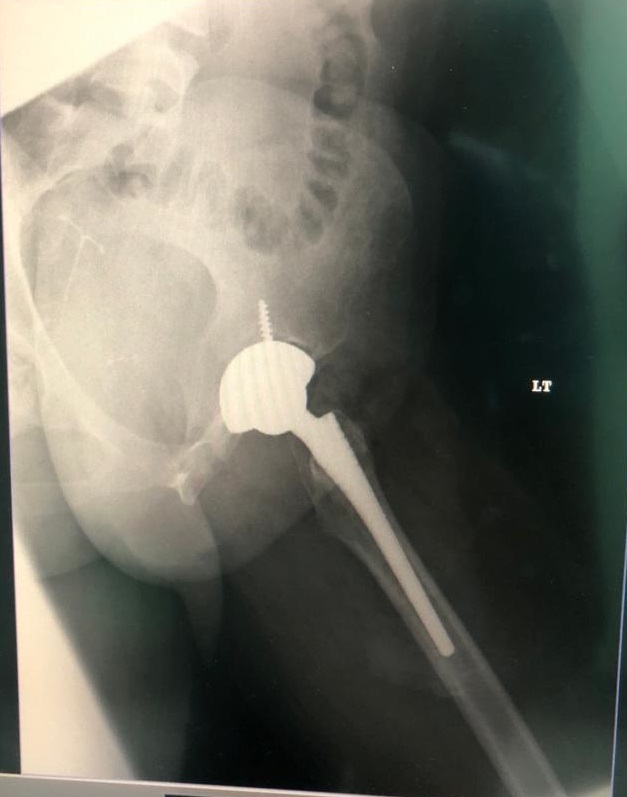

Patient 23

38 year old with avascular necrosis of the hip

Ceramic on poly articulation